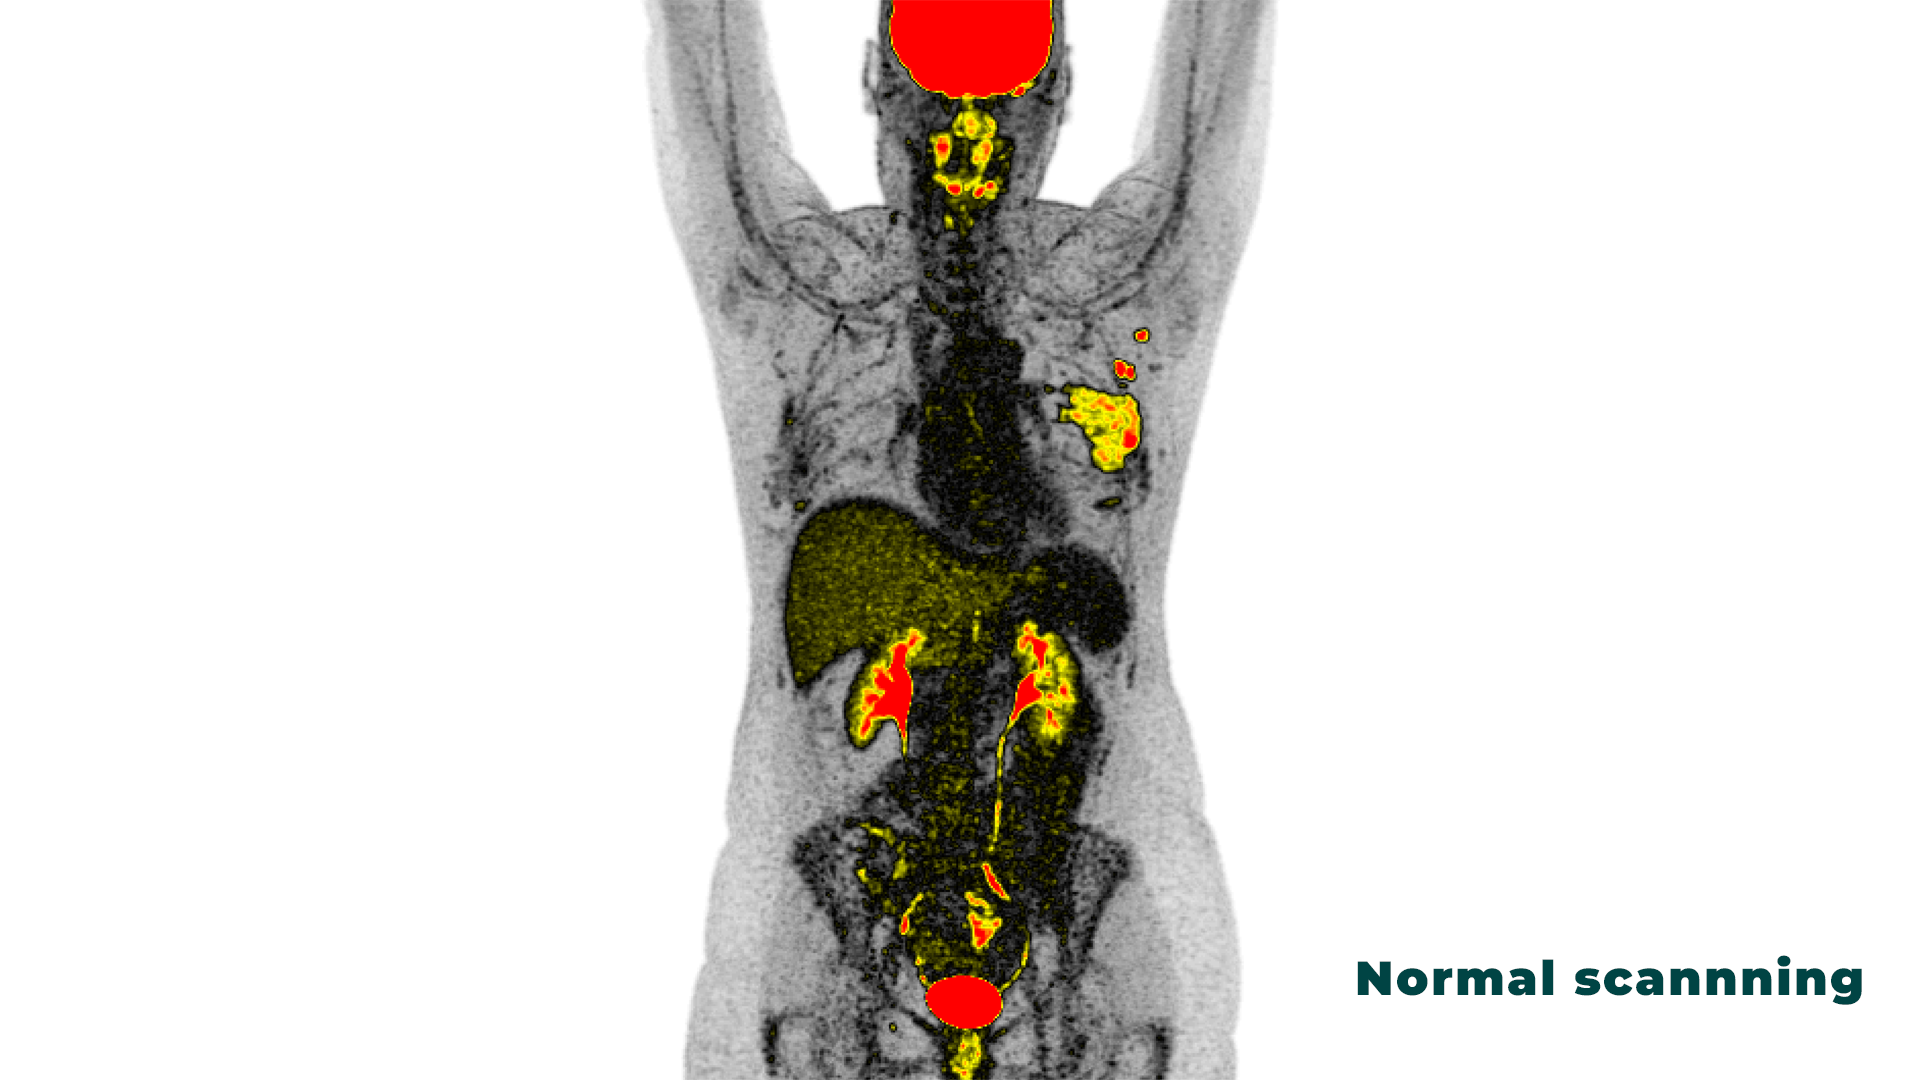

NoloSight’s ProPET is an advanced probabilistic reconstruction and image analysis methodology specifically designed to enhance lesion detection in PET/CT imaging. By combining informed prior models with machine learning, ProPET improves the ability to identify small lesions while maintaining clinical accuracy.

Enhanced Lesion Detection

ProPET identifies additional suspicious foci across all anatomical regions, particularly excelling at detecting small lesions that may be obscured by noise and smoothing artifacts in conventional reconstruction. In clinical evaluation, ProPET consistently identified more lesions while missing none that were detected with standard reconstruction.

Improved Diagnostic Confidence

The posterior probability distributions generated by ProPET provide uncertainty estimates and lesion probability maps at each voxel, enabling clinicians to distinguish confident findings from borderline cases. This enhanced confidence supports more decisive clinical decision-making.

ProPET’s development has focused on FDG-PET/CT imaging in oncology, with particular emphasis on improving detection of: